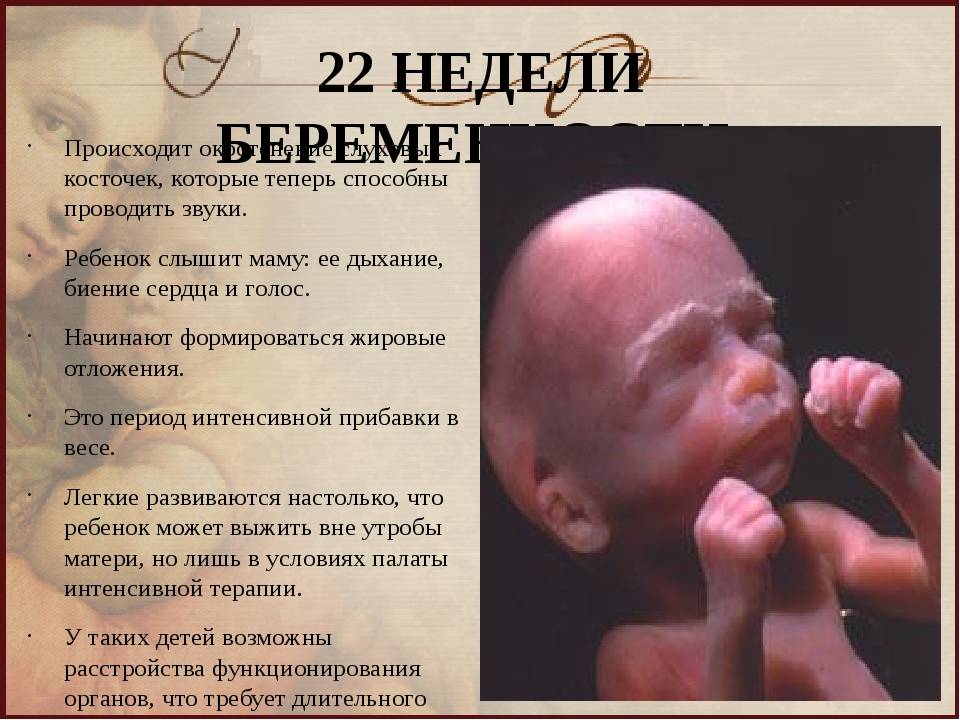

Слуховое развитие

На 22 неделе беременности ваш малыш активно развивает слуховую систему. В это время его ухи уже сформированы и находятся на правильном месте. Ребенок начинает слышать звуки из внешнего мира и реагировать на них.

С помощью слухового аппарата вашего ребенка можно сравнить с небольшим приемником, который способен регистрировать звуки. На данный момент его ушки могут воспринимать звуковые колебания и передавать их в мозг. Это позволяет малышу слышать и распознавать голос мамы, звуки сердцебиения, шумы окружающей среды и даже музыку. Ваш голос становится особенно важным и знакомым для ребенка.

Что происходит с малышом на 22 недели беременности

- В этот период волосы малыша отрастают с особой интенсивностью, но их цвет еще не выражен – пока недостаточно меламина вырабатывает его маленькое тельце.

- Быстро развивается головной мозг. Именно в это время малыш начинает изучать себя и то, где он находится с помощью тактильных ощущений. Именно на 22 неделе беременности ребенок пробует шевелить пальчиками, касаться стенок плаценты и себя. Такое исследование ребенком пространства своего обитания будет усиливаться именно на 22 неделе, так что беременная мама будет хорошо ощущать его прикосновения.

- На стадии 22 недели ребенок в утробе матери останавливает свой рост в высоту. В дальнейшем происходит формирование рефлекторных мышц, они усложняются с каждым днем. Мозговые клетки уже почти сформировались, и мозг весит порядка 95 – 100 г.

- В этот период у ребенка начинается развитие желез внутренней секреции, в частности, потовых желез.

- Продолжают активно формироваться кости – кальций все больше накапливается и откладывается в организме младенца. В связи с этим беременным женщинам прописывают специализированные препараты, содержащие большое количество кальция.

- На 22 неделе беременности развитие позвоночника плода завершает свое формирование. К окончанию второго триместра все позвонки и межпозвоночные диски уже полностью образованы.

- Во время планового УЗИ на 22 неделе беременности на тельце малыша появляются еле заметные волосики, похожие на пух. Они формируют некий вакуум вокруг плода, задерживающий первородную смазку. Кроме этого, смазка защищает ребенка от соприкосновения с водной средой околоплодных вод. Непосредственно перед родами, волосики за ненадобностью исчезают, а предродовая смазка обеспечивает легкий выход малыша из утробы матери.

- Уже на 22 неделе ребенок должен шевелиться, подавая определенные знаки. Теперь уже это непросто проявления рефлекторной физической активности – это осмысленный анализ окружения и обстановки. В это время плод становится очень чувствительным ко всем внешним раздражителям, шуму, музыке разговору, свету и даже свежему воздуху. Теперь он уже непросто переворачивается и изучает окружающую его среду – он выражает свое недовольство или одобрение бурными движениями. Иногда, частое кувыркание младенца в утробе может свидетельствовать о недостатке кислорода, поэтому мамочке нужно трепетно прислушиваться к знакам и вовремя на них реагировать. Но не стоит перебарщивать, воспринимать любое движение ребенка в качестве недовольства или желания. Во время сна, а это большая часть времени, малыш не активен. Зато утром и вечером может разводить бурную деятельность. Проблема в том, что биологические часики плода не всегда совпадают с фактическими утренними и вечерними часами. Это для мамы не всегда комфортно. Слишком спокойное поведение ребенка тоже должно немного настораживать, а в отсутствие малейших движений более двух суток – нужно обязательно показаться врачу.

Какие изменения происходят с плодом на 22 неделе беременности?

На 22 неделе беременности плод продолжает развиваться и весит уже около 450 граммов. Его длина составляет примерно 27 см. Наблюдается активное формирование мозга и нервной системы, а также развитие мышц и костей. Появляются пальчики на ногах и руках, формируются пальцы. Органы слуха продолжают развиваться, а кожа покрывается слоем мягкого волосяного покрова.